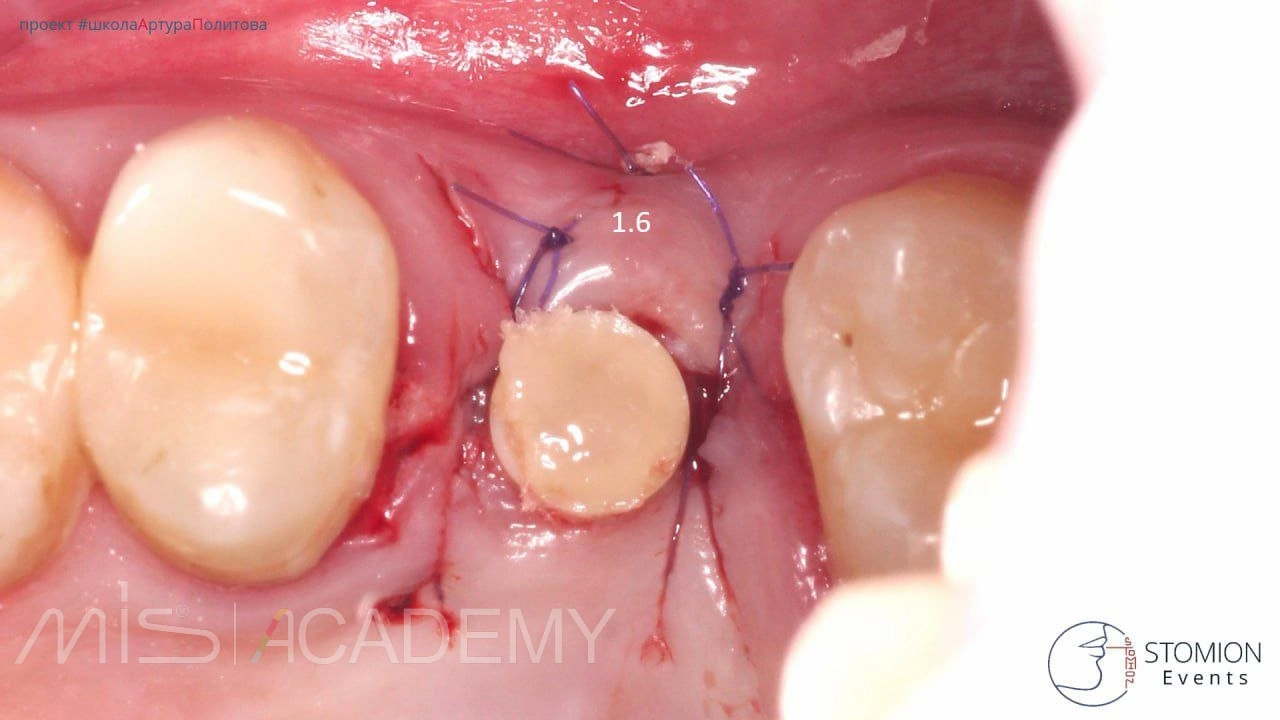

Имплантация MiS C1, 1.6 + ЗСЛ, 4.6.

— 1.6 — торк 35 Н/см, установлен PIC абатмент вместо ФДМ. Мягкие ткани рол-техника.